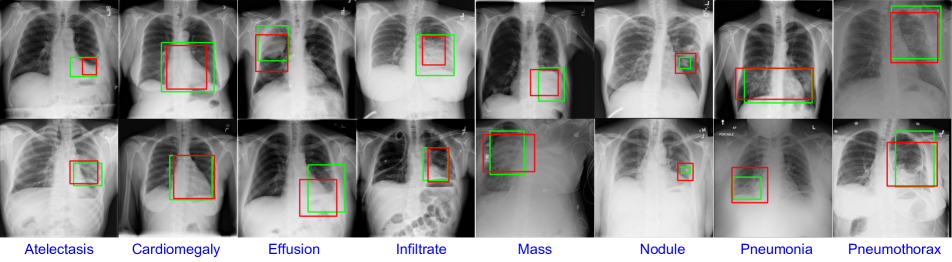

Refer to caption

Figure 1: Examples of the disease localizations generated from our network. The localization output from our network (red bounding box), that trained only with image-level annotation, match with the ground truth localization (green bounding box).